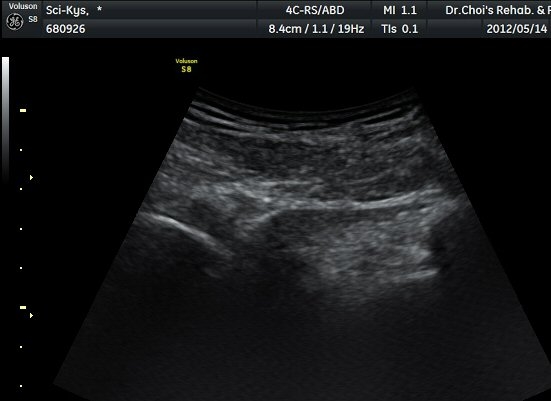

¾ûµ¢ÀÌ Á°ñ¿¡¼­ Á°ñ½Å°æ Ⱦ´Ü¸é°Ë»ç¿¡¼­ ´ëµÐ±Ù°ú quadratus femoris »çÀÌÀÇ ±Ù¸·

°æ°èºÎ¿¡¼­ Á°ñ½Å°æÀÌ °üÂûµÇ´Âµ¥ ³»Ãø Á°ñ°áÀý(ischial tuberosity) ÃøÀ¸·Î Ä¡¿ìÃÄ

ÀÖ´Â °ÍÀ¸·Î ÆÇ´ÜµÈ´Ù(±×¸² 1, 2, 3).

Á¤»óÃø(±×¸² 6, 7)°ú ºñ±³Çϸé Á°ñ½Å°æÀÇ ³»Ãø ÀüÀ§°¡ ¶Ñ·ÈÇÏ´Ù.